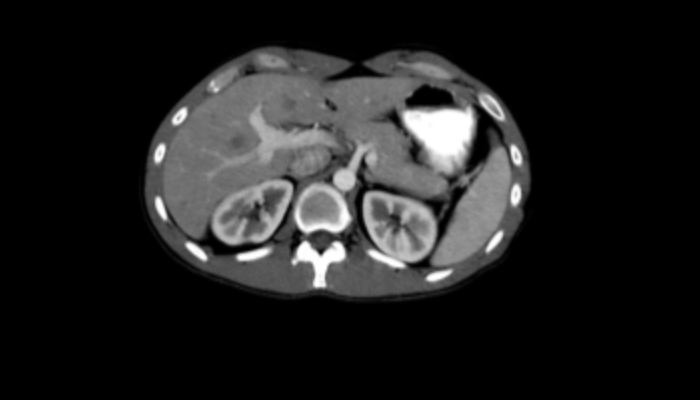

頭部CT画像 頭部CT脳出血や脳挫傷などの評価を行います。 胸部CT画像 胸部CT肺がんや肺炎や大動脈など胸部臓器を評価します。 心臓CT画像 心臓CT冠動脈を評価し、狭心症や心筋梗塞のリスクを検索します。 腹部CT画像 腹部CT肝臓・胆のう・膵臓・腎臓など腹部の重要臓器を評価します。 骨・関節CT画像 関節・骨CT骨折の評価に優れます。 動静脈CT画像 動脈・静脈CT動脈瘤や閉塞性動脈硬化症、深部静脈血栓症など血管の評価を行います。 大腸CT 大腸CT仮想内視鏡と言われる大腸の3D画像を得ることで苦痛の少ない大腸検査をすることができます。検査前日より検査食と下剤を服用していただきます。